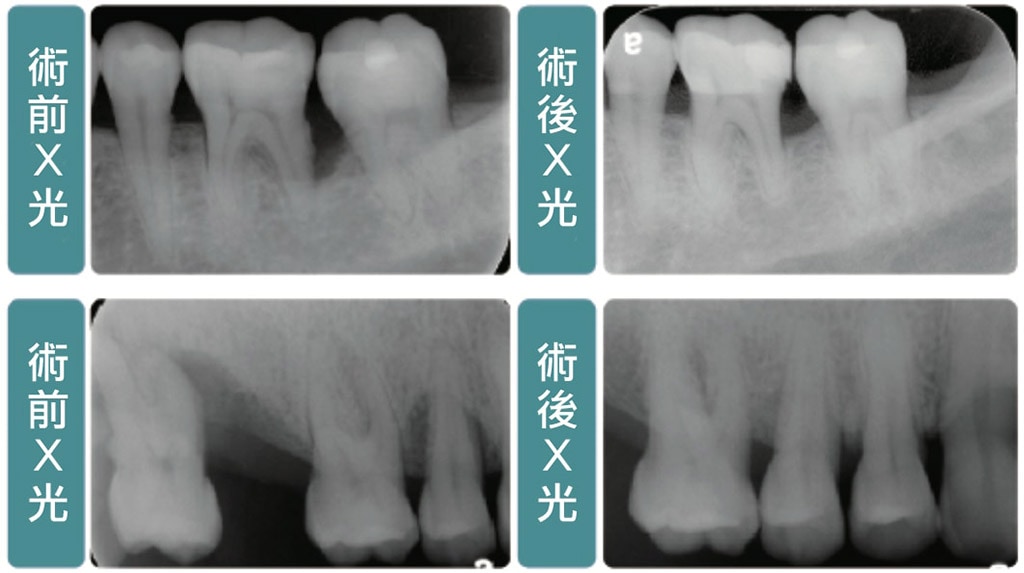

牙周手術案例之三 自強牙醫部落格